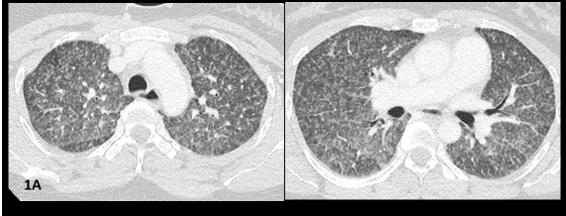

At day seven, she was transferred to the ICU due to sudden worsening respiratory failure (RF) (tachypnea, PaO2/ FiO2<100mmHg). Empirical piperacillin/tazobactam and azithromycin were added, presuming superimposed hospitalacquired bacterial infection. After an unsuccessful 16-hour trial of high-flow oxygen therapy, she was intubated and mechanically ventilated (Vt 6ml/kg, PEEP 10cmH20). CT angiogram ruled out pulmonary emboli and air-leak syndromes, showing worsened micronodules and new-onset symmetrical ground glass opacities with anteroposterior density gradient and small bilateral pleural effusion (Figure1B).

Figure 1B: CTPA images. Worsening of micronodules and appearance of symmetrical ground glass opacities with anteroposterior density gradient; small bilateral pleural effusion.